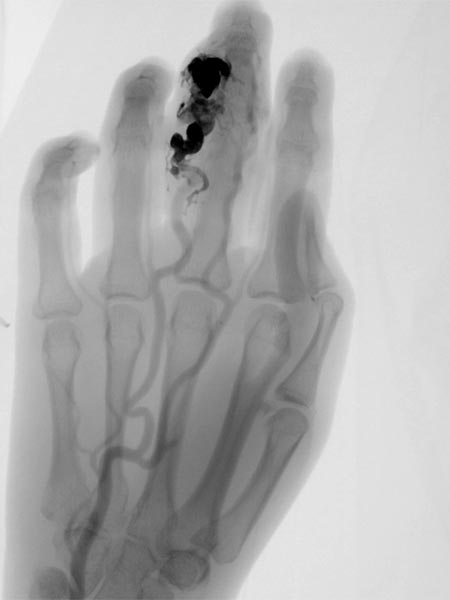

Fluoroscopic control after successful nidus embolization of the AVM. The transarterially inserted microcatheter was left in place during percutaneous embolization as a landmark for the feeding digitalis propria artery. In addition, radiopaque markers are displayed by gauze placed on the skin.

Angiographic control of the right hand with catheter injection from transarterially via the ulnar artery. Complete devascularization of the AVM nidus. No fast-flow shunts can be angiographically detected. The treated AVM with occluded nidus is thus resectable.

Fluoroscopic view of the cast after successful nidus embolization of the AVM. To improve the overview for surgical planning, this image is also shown without subtraction with visible bone.